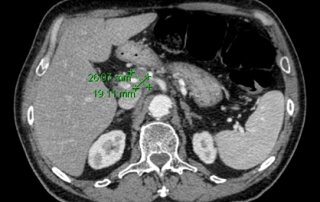

Imagerie évaluation de la réponse :

La biopsie guidée sous scanner de la masse mésentérique conduit au diagnostic de lymphome diffus à grandes cellules B CD20+ avec des zones évoquant la transformation d’un lymphome folliculaire en lymphome agressif.

Biologie : hémogramme normal, LDH augmentées à 720 UI. Biopsie médullaire et le myélogramme et l’immunophénotype médullaire montre une infiltration médullaire par un lymphome folliculaire à petites cellules, l’examen cytogénétique retrouve une translocation t(14 ;18), et l’étude en biologie moléculaire un réarrangement du gène Bcl2.

Classement LNH diffus à grandes cellules CD20+ transformation d’un lymphome folliculaire, stade IV péritonéal et médullaire, OMS = 1, LDH augmentées. L’infiltration médullaire à petites cellules caractérise la transformation du lymphome folliculaire, et n’a pas la valeur pronostique péjorative d’une infiltration médullaire d’un lymphome à grandes cellules.

Décision Traitement initial par R-ACVBP x 4 cycles avec prophylaxie neuro-méningée. Recueil d’un greffon CSP après 4ème cycles. Consolidation par métothréxate à hautes doses et conditionnement BEAM autogreffe de cellules souches sous réserve d’obtention d’une réponse complète